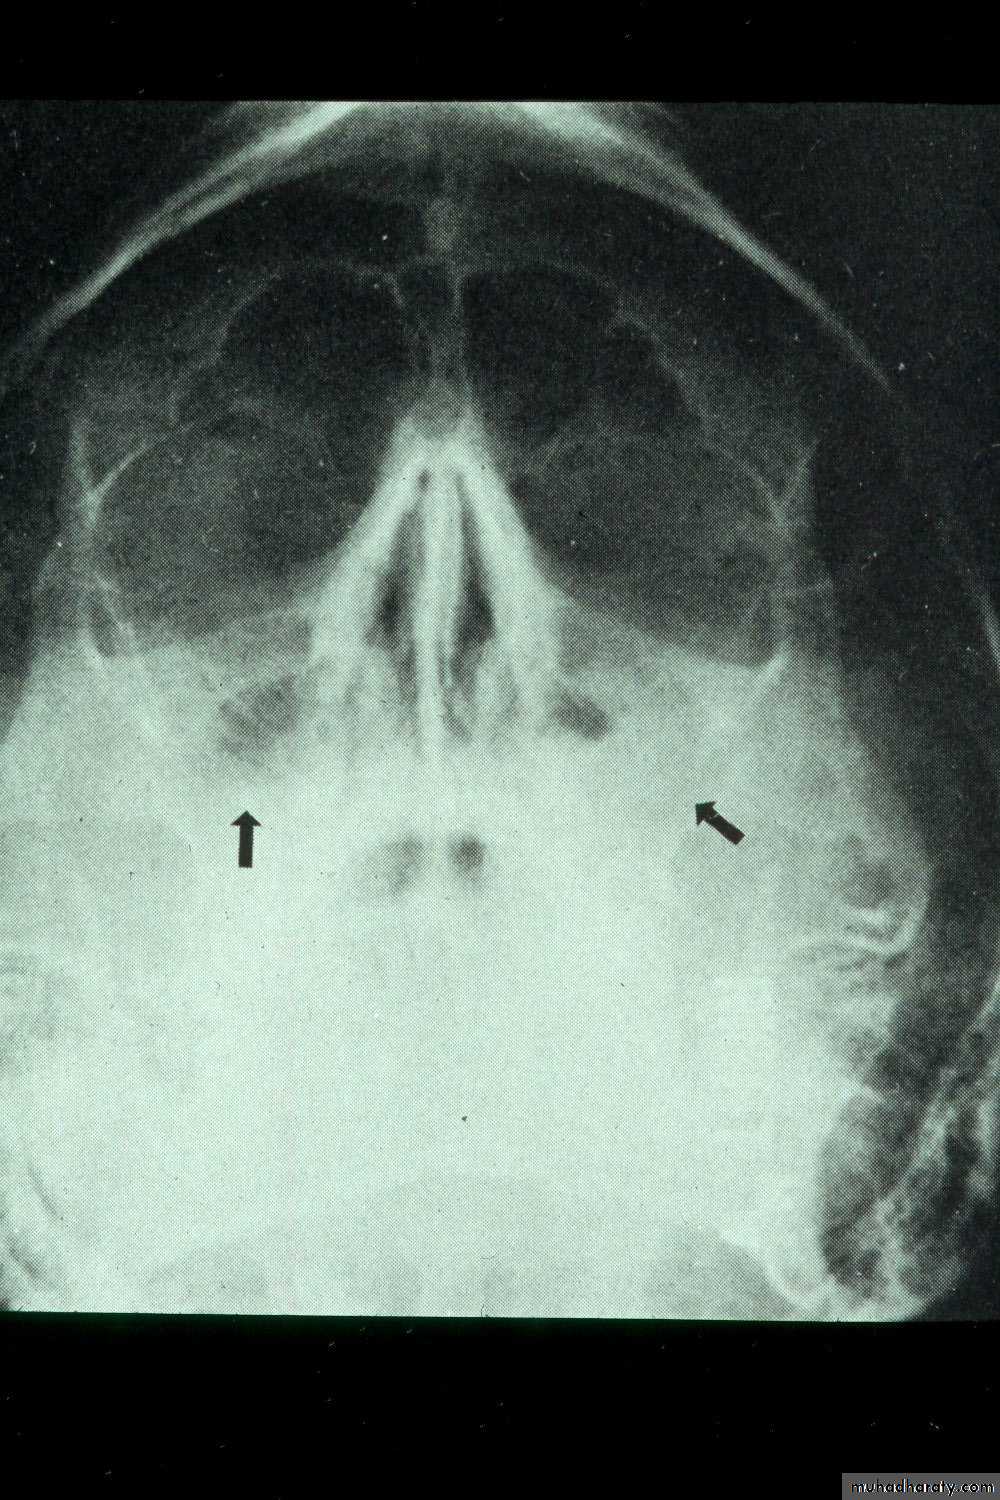

• Occipitomental View (15° OM): it’s called Water’s view. The presence of pus will produce a horizontal fluid level in this view; provided that there is air above it. As a measure of confirmation of the diagnosis, the view is repeated with the head tilted toward the side of pathology. The fluid level remains horizontal.

Water’s view showing air-fluid level in right maxillary sinus and mucosal thickening in left maxillary sinus